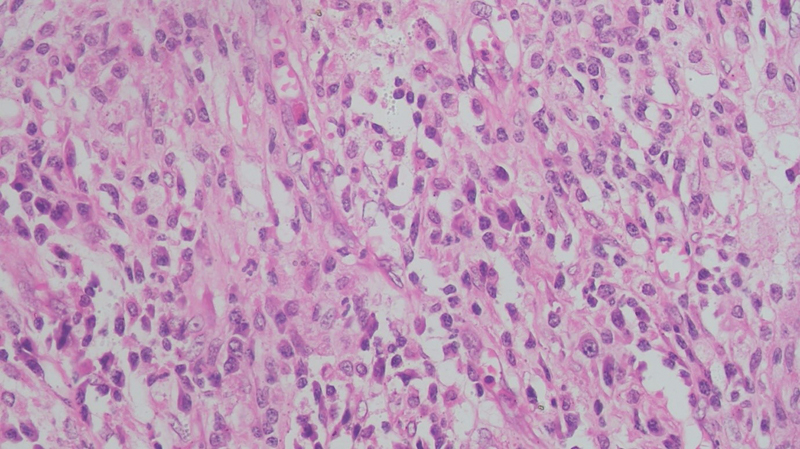

On microscopic examination, the cyst wall was seen to be comprising of fibrocollagenous tissue, infiltrated by sheets of foamy macrophages, lymphocytes, plasma cells, and neutrophils ([Fig. 1], [2], [3]). Proliferating blood vessels were noted. Few areas showed fibrosis with hemosiderin-laden macrophages. Endometrial glands or stroma was not seen. The features like atypia and dysplasia were characteristically absent. The appendix showed normal histomorphology with periappendiceal inflammation. CD68 immunohistochemistry confirmed the presence of foamy histiocytes ([Fig. 4], [5]), while pan-cytokeratin was negative. Diagnosis of xanthogranulomatous oophoritis was made, based on the histomorphological features.

| Fig. 1 The presence of large number of foamy histiocytes admixed with plasma cells, lymphocytes, and occasional neutrophils, is seen, which is pathognomonic feature of xanthogranulomatous oophoritis (hematoxylin and eosin staining; magnification 100x).

The gross appearance of the specimens may show cystic degeneration, foci of necrosis, and hemorrhage, in grossly enlarged ovary. The microscopic examination shows the presence of foamy histiocytes, along with a mixture of inflammatory cells like lymphocytes, plasma cells, and occasional neutrophils.[21] Foamy histiocytes, the so-called “xanthoma cells,” are histiocytes with abundant lipid-laden cytoplasm having a vacuolated appearance. These impart the yellowish color to the specimen, when seen on the gross examination. There is no cellular atypia, abnormal mitoses, or any other microscopic feature suggestive of malignancy.